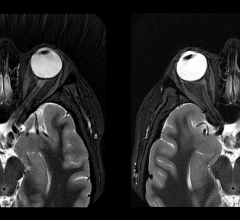

January 27, 2023 — According to an accepted manuscript published in ARRS’ American Journal of Roentgenology (AJR), both ...